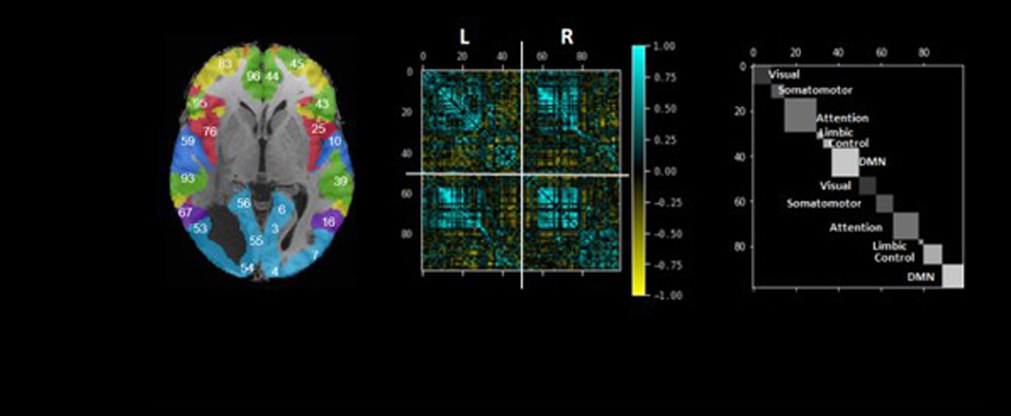

17. Juli 2024 - Einblicke in die Basalganglien-Thalamo-kortikale Konnektivität bei Major Depression mittels 7T fMRI

20. Mai 2024 - Neue Studie unterstreicht die Bedeutung von sozialer Unterstützung und psychologischer Belastbarkeit für die funktionelle Konnektivität im Gehirn

13. Mai 2024 - Einblicke in die Veränderungen der Mikrostruktur des Gehirns über die Lebensspanne hinweg

8. Februar 2024 - Überprüfung von Submillimeter-fMRI-Erfassungstechniken zur Erkennung von Hirnaktivierung auf laminarer und säulenförmiger Ebene